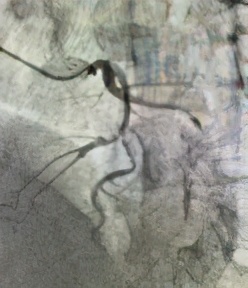

杨某,男,68岁,“因反复胸闷一周”入院,入院后行冠脉造影术,透视下见冠脉严重弥漫性钙化,右冠中段闭塞;前降支近段到中段严重95-99%弥漫性狭窄,病变处发出粗大第二对角支,第二对角支开口到近段95-99%弥漫性狭窄,属于真性分叉病变伴严重钙化;回旋支近段80%弥漫性狭窄,发出丰富侧枝循环供应右冠。患者命悬一线!刘杰主任率先对前降支分叉病变预处理后,在OCT指导下完成了分叉支架手术(culottes),术后OCT结果显示分叉支架贴壁良好,术后患者胸闷立即改善。

钙化及分支血管

最小管腔

术前